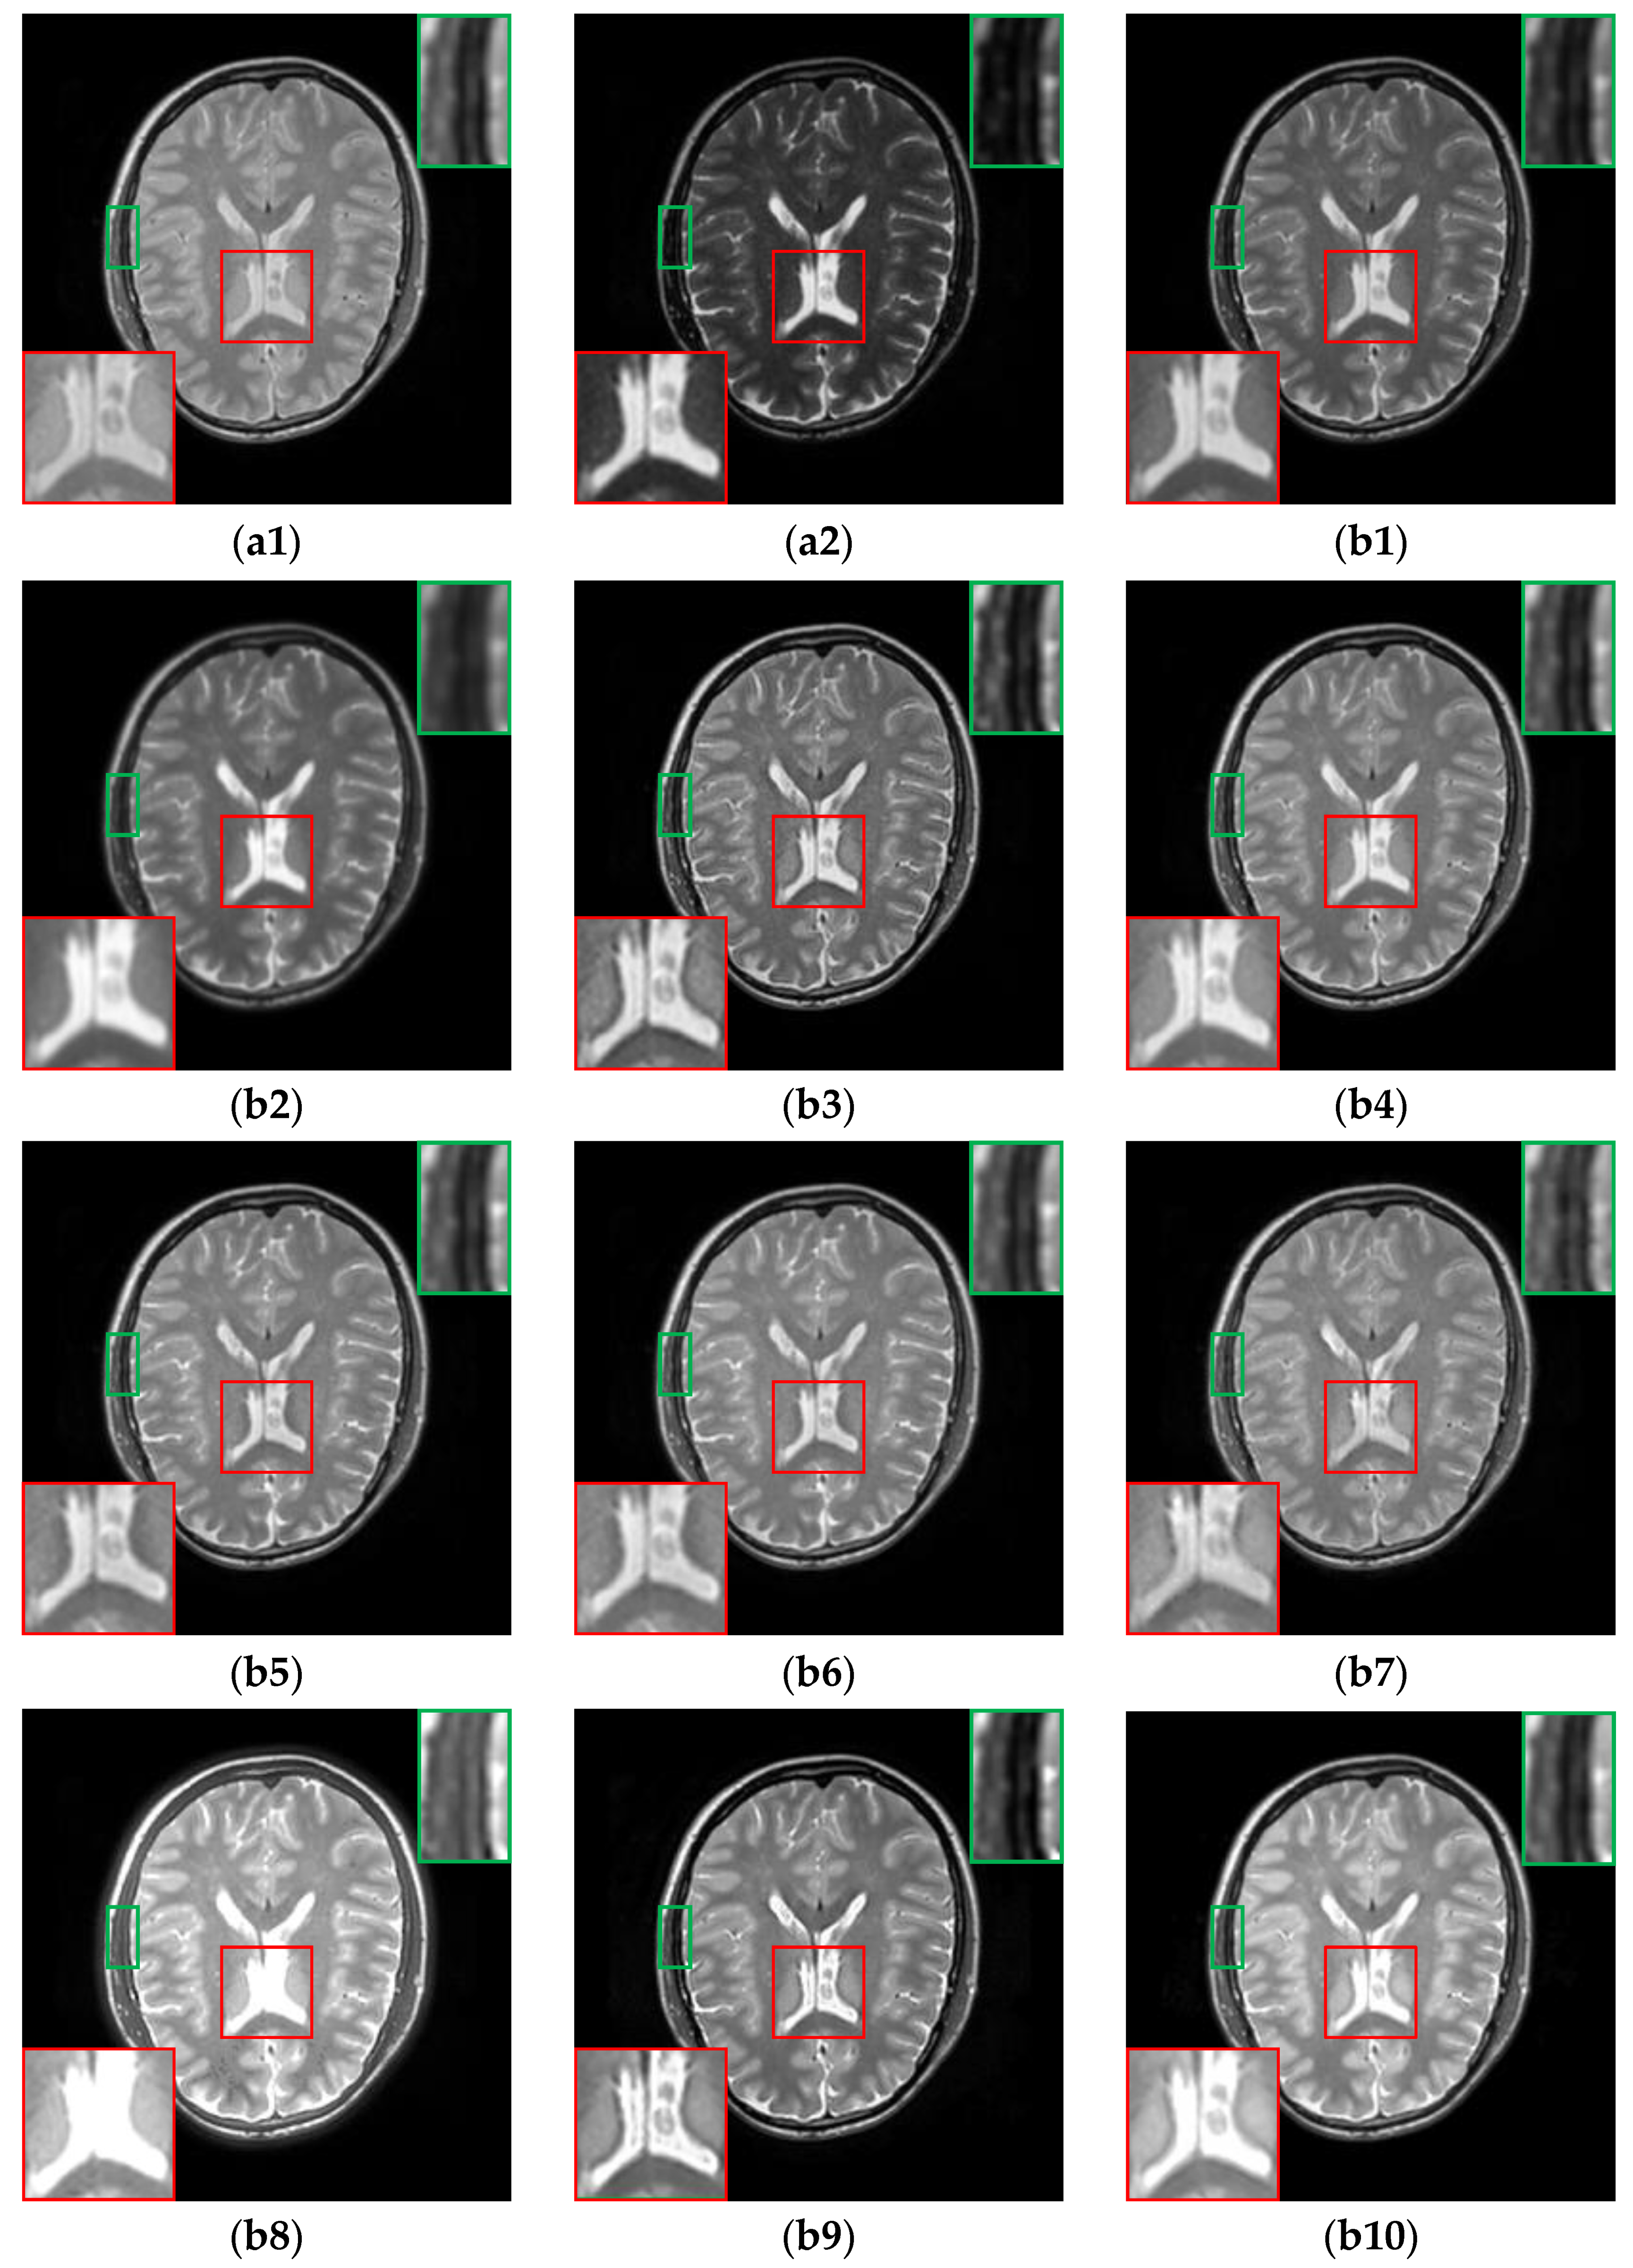

The fusion results of multi-modal MR (i.e., T1 and T2) image pairs from the Atlas dataset are shown in Figure 5. Generally, except for TIF, CDDFuse and CIRF, the brightness and intensity of all other algorithms are insufficient. Specifically, from the areas marked by the red boxes, the upper parts of the brainstem are blurred or missing in the fused results of U2Fusion, DenseFuse, RFN-Nest, PAPCNN, ReLP and CDDFuse. Additionally, as labeled by the green boxes, except for CDDFuse and CIRF, all other methods produce blurry and incomplete boundaries of the occipital lobe. By comparison, the CIRF algorithm performs better than other algorithms in terms of edge preservation.

Figure 5. The results of all algorithms on the multi-modal image pairs from Atlas dataset. (a1) Source T1 image; (a2) Source T2 image; (b1) U2Fusion; (b2) DenseFuse; (b3) IFCNN; (b4) NestFuse; (b5) RFN-Nest; (b6) PAPCNN; (b7) ReLP; (b8) TIF; (b9) CDDFuse; (b10) CIRF.